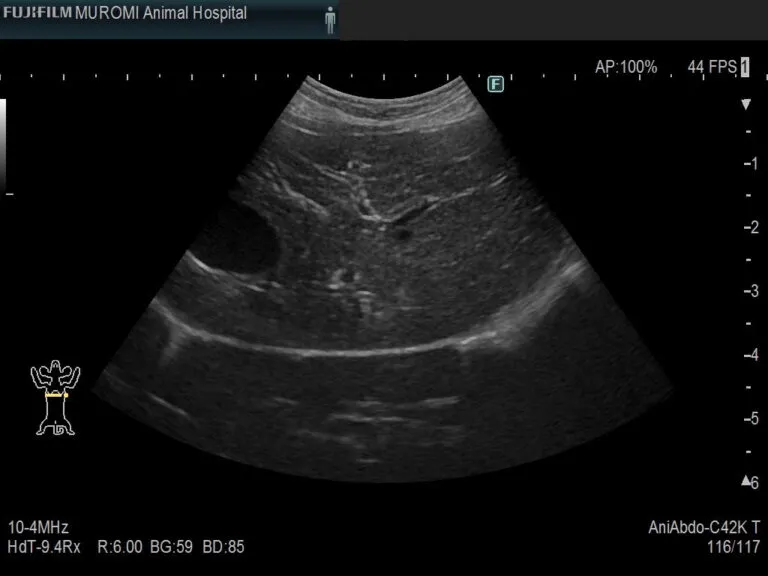

◎腹部エコー検査・・・肝臓実質、門脈や後大静脈、胆嚢や胆管の状態を調べると同時に、周囲の腸管や膵臓、腹水の有無を確認します。

肝臓エコー画像